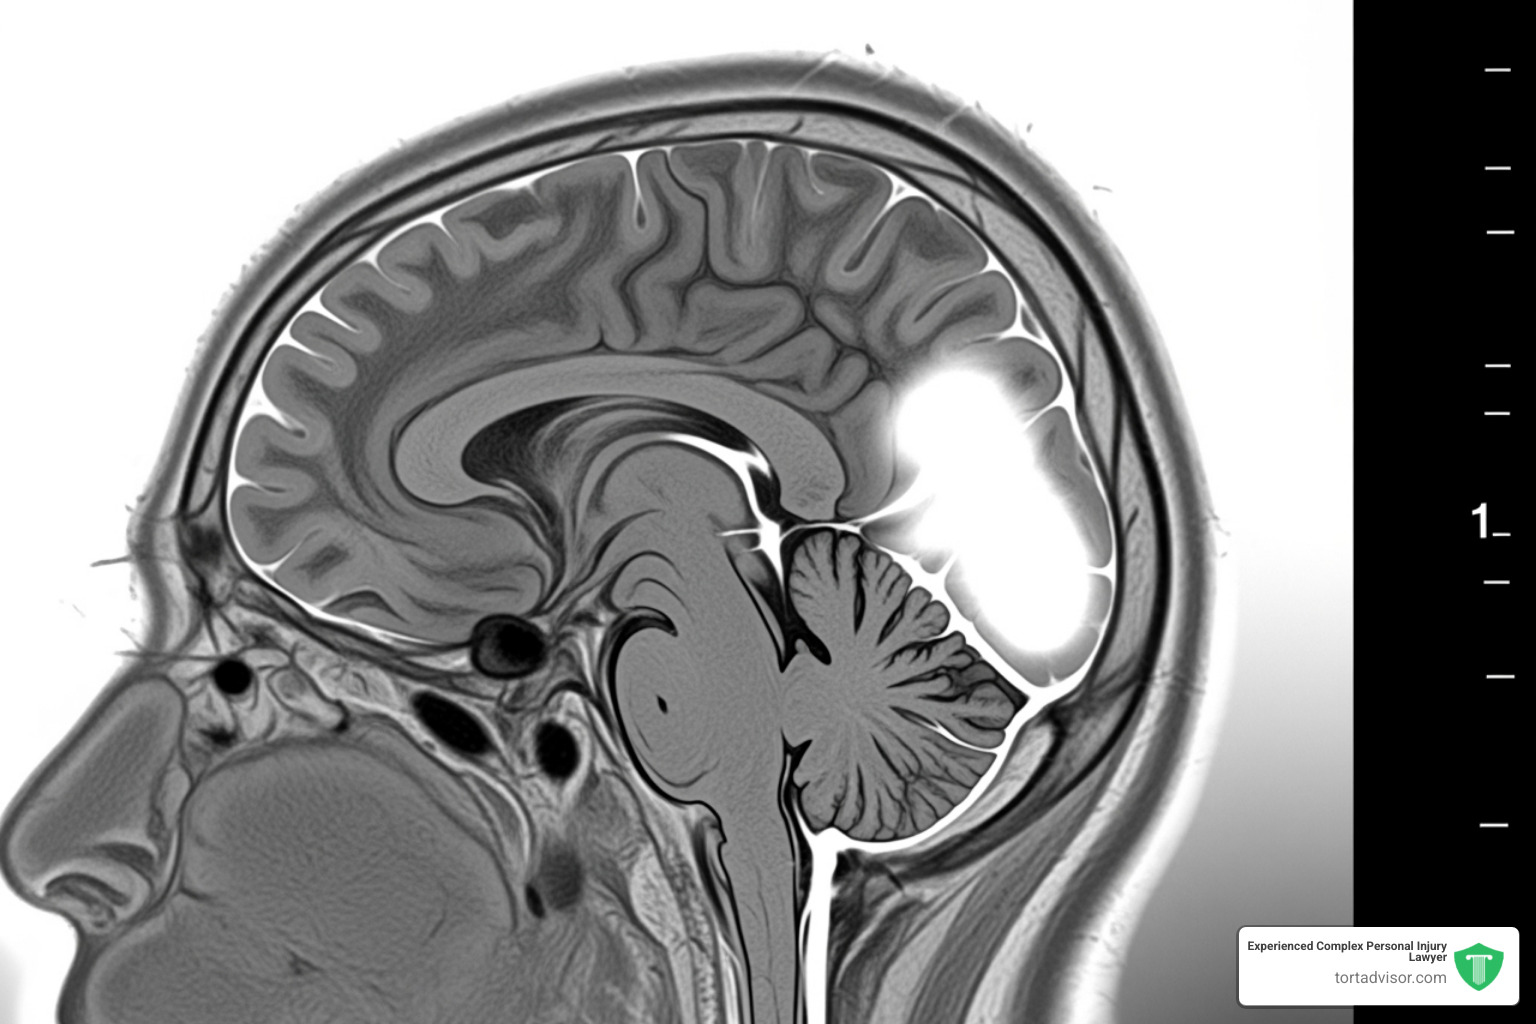

The risk involves meningiomas, tumors that grow in the protective membranes around the brain and spinal cord. According to the Mayo Clinic, they are the most common type of head tumor. Though usually benign (non-cancerous), meningiomas can grow large enough to press on the brain, causing severe health problems.

- Formal Diagnosis: A medical professional must have formally diagnosed you with a meningioma, usually confirmed by an MRI or CT scan.

- Location: Lawsuits focus on intracranial meningiomas—tumors inside the skull. The scientific evidence is strongest for these tumors.

- Complete Medical Records: All documents related to your diagnosis and treatment, including imaging results (MRIs, CT scans), pathology reports, and detailed doctor’s notes.